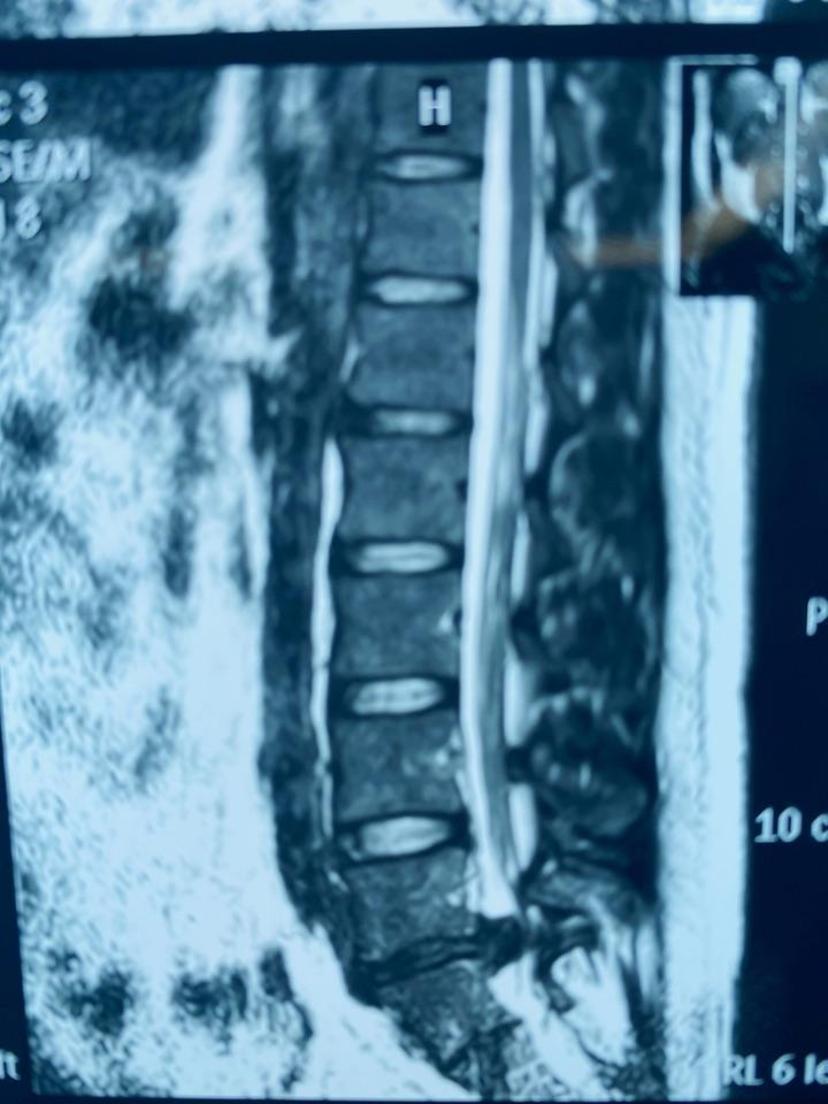

患者因腰痛诊断出腰5-骶1椎间盘突出5年了,这四天来腰背部疼痛难忍,双下肢麻木无力,会阴部麻木,不能站立、不能平躺,大小便排出困难,再次复查腰椎磁共振:腰5-骶1椎间盘全部脱出于椎管内导致椎管狭窄,双侧神经及硬膜囊完全受压,急诊采用双侧减压方式,取出串珠状游离的髓核组织,术后第三天恢复排便功能,大小便基本正常,症状解除,神经功能得到恢复!温馨提醒:(如果您患有腰椎间盘突出,突发腰痛及双下肢痛麻症状加重,出现会阴区麻木,性功能下降、大小便失禁或排出障碍,很可能就是椎间盘脱出导致的马尾综合症,建议尽快到正规医院脊柱外科就诊,防止不可逆的马尾神经损伤导致的严重后果)。腰5-骶1椎间盘脱出占满椎管全部空间,硬膜囊完全受压

磁共振平扫显示椎间盘脱出压迫硬膜囊